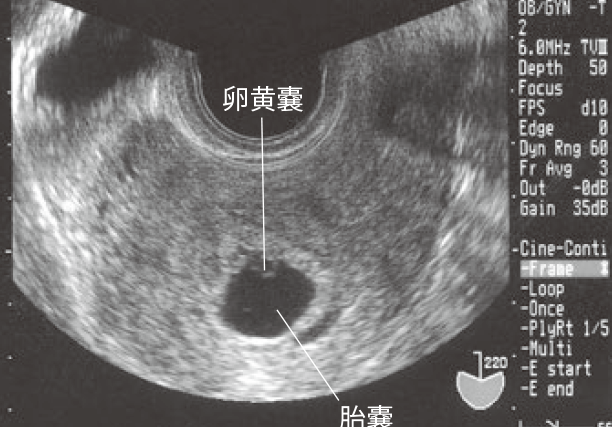

卵黄嚢は胚発生において重要な役割を果たす構造です。発生中、卵黄嚢は栄養供給の役割を担い、発育を助けるための細胞を蓄えています。この部分は、細胞分裂の初期段階において、胚を形成する上で欠かせません。また、卵黄嚢は酸素や栄養素の供給を行うため、胚の成長を支援します。

胚盤胞内で、細胞が集まって卵黄嚢を形成します。この段階では、栄養物質が蓄積されます。

卵黄嚢が成長し、胚に栄養を供給しながら、重要な役割を果たします。